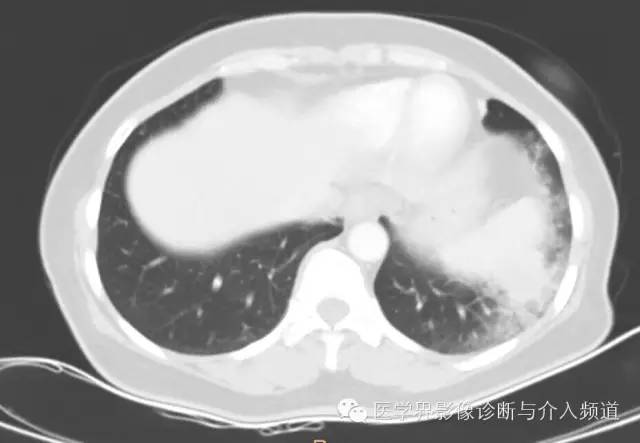

左下肺硬化性血管瘤1例CT影像表现

女性,59岁,三天前无诱因出现咳嗽,痰中带血,量不多,无气短喘息,无胸痛,无盗汗自汗,自发病以来,无发热寒战,无心悸,胸憋,无咳浓臭痰,无头痛呕吐,来我院就诊,行CT检查。

左肺下叶可见软组织密度肿块影,形态不规则,边界不光整,与胸膜粘连不清,周围肺组织呈磨玻璃密度改变,病变内部不均匀强化,低密度区不强化。

硬化性血管瘤